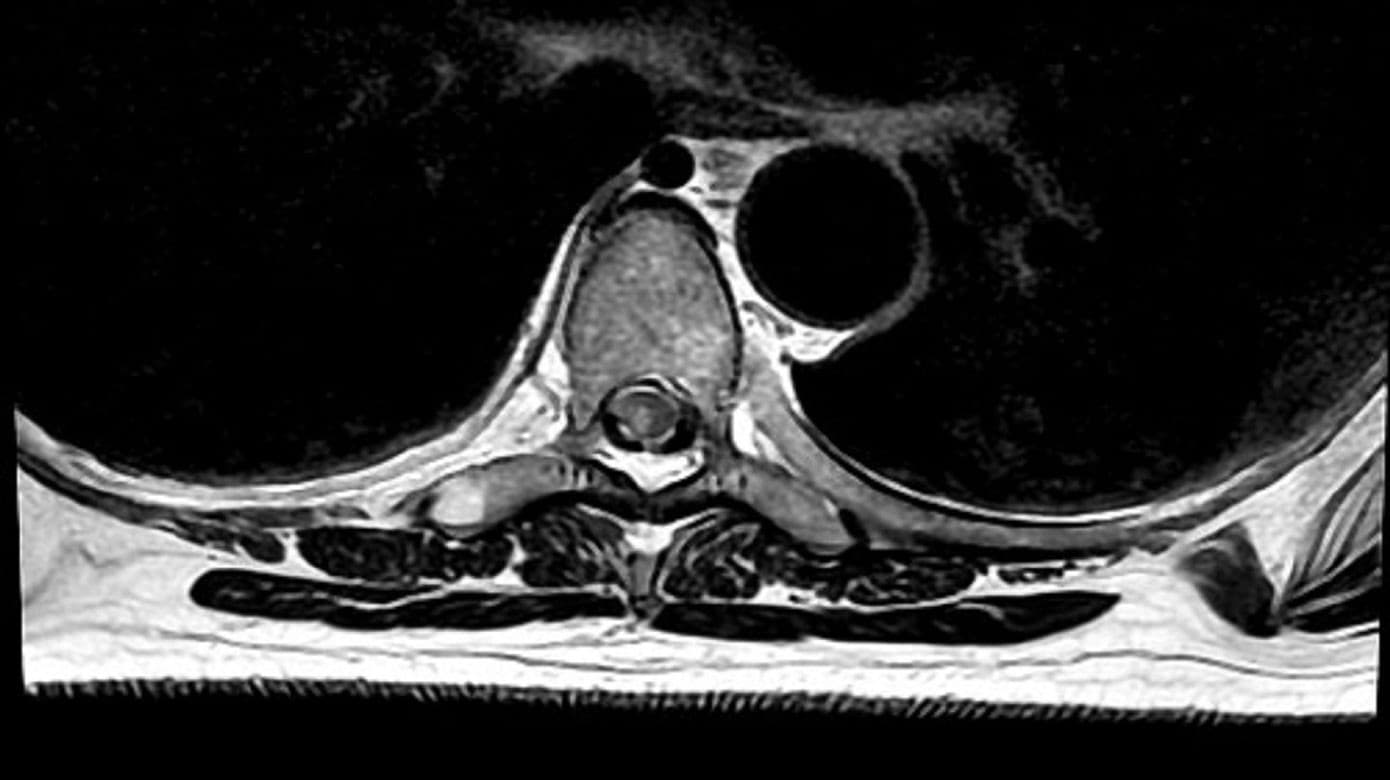

MR-skanning af columna totalis viste et akut infarkt i forsyningsområdet for højre a. spinalis posterior ud for Th5-Th10 (Figur 1). Patienten blev opstartet i acetylsalicylsyre 75 mg en gang dagligt i 21 dage samt clopidogrel 75 mg dagligt livslangt.